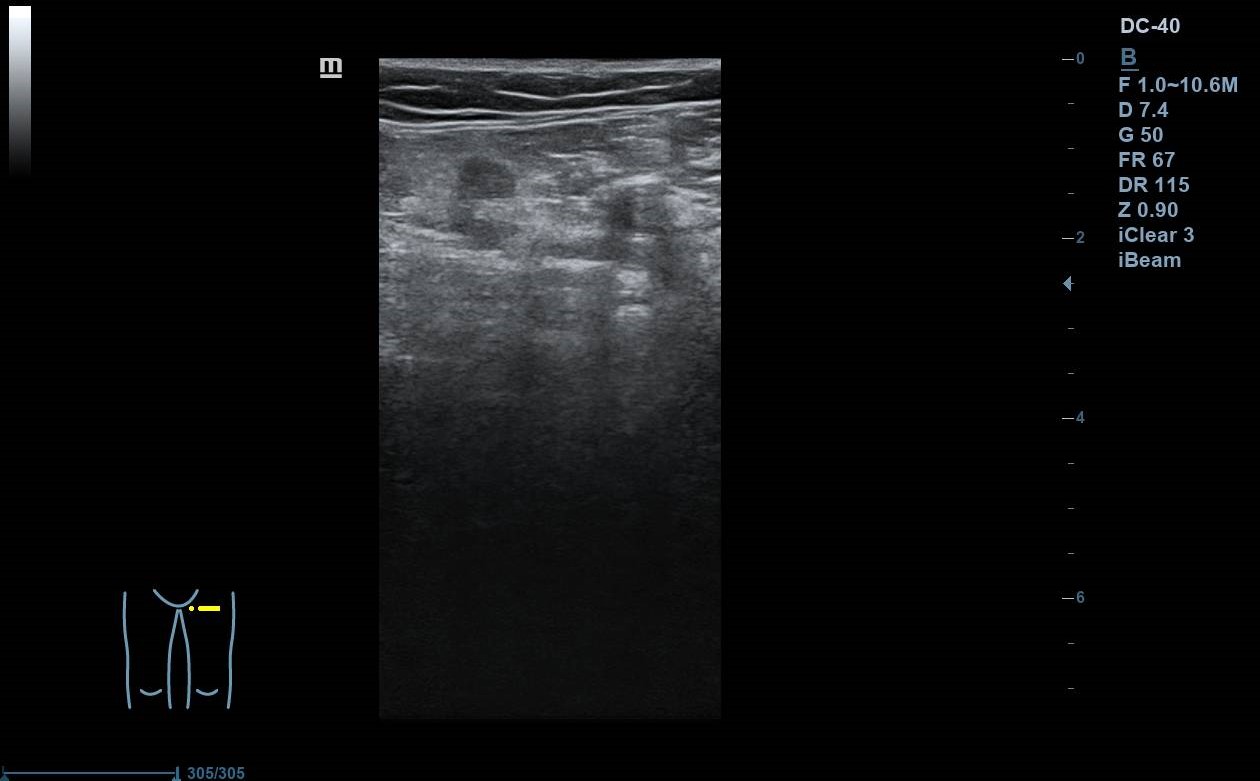

Se realiza ecografía Doppler en el Centro de Salud: se exploran con sonda lineal ambos MMII a nivel inguinal y poplíteo, constatando colapsabilidad, presencia de flujo y ausencia de material ecogénico a nivel de vena femoral común y poplítea. Colocando sonda en el punto doloroso observamos vena safena interna no colapsable. Nos desplazamos superiormente, siguiéndola hasta la unión safenofemoral, sin observar colapsabilidad durante el trayecto.

Juicio clínico: TVS en vena safena interna de al menos 5 cm con afectación próxima a cayado.